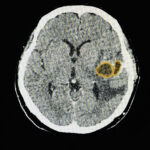

Bildgebende Verfahren liefern entscheidende Erkenntnisse über das Ausmaß und die Auswirkungen von Helmintheninfektionen. Mit Ultraschall lassen sich Zysten oder Läsionen, die durch Parasiten wie Echinococcus verursacht werden, sehr gut sichtbar machen. Radiologische Bildgebungsverfahren wie Röntgenaufnahmen und Computertomografien (CT) bieten detaillierte Einblicke in strukturelle Veränderungen und mögliche Komplikationen infolge von Infektionen. Diese Techniken sind besonders wertvoll für die Diagnose von Krankheiten wie Taeniasis, bei der die Feststellung des Vorhandenseins von Bandwürmern von entscheidender Bedeutung ist.

Die Taeniose, die durch Bandwurminfektionen im Darm verursacht wird, äußert sich häufig durch leichte Bauchbeschwerden und Gewichtsverlust. Die Zystizerkose hingegen, bei der sich Zysten in verschiedenen Geweben, einschließlich Gehirn und Muskeln, bilden, ist durch schwerere neurologische Symptome, Krampfanfälle und sogar kognitive Störungen gekennzeichnet. Die beiden Erkrankungen sind ein Beispiel für die komplizierten Variationen von Helminthen-Infektionen.